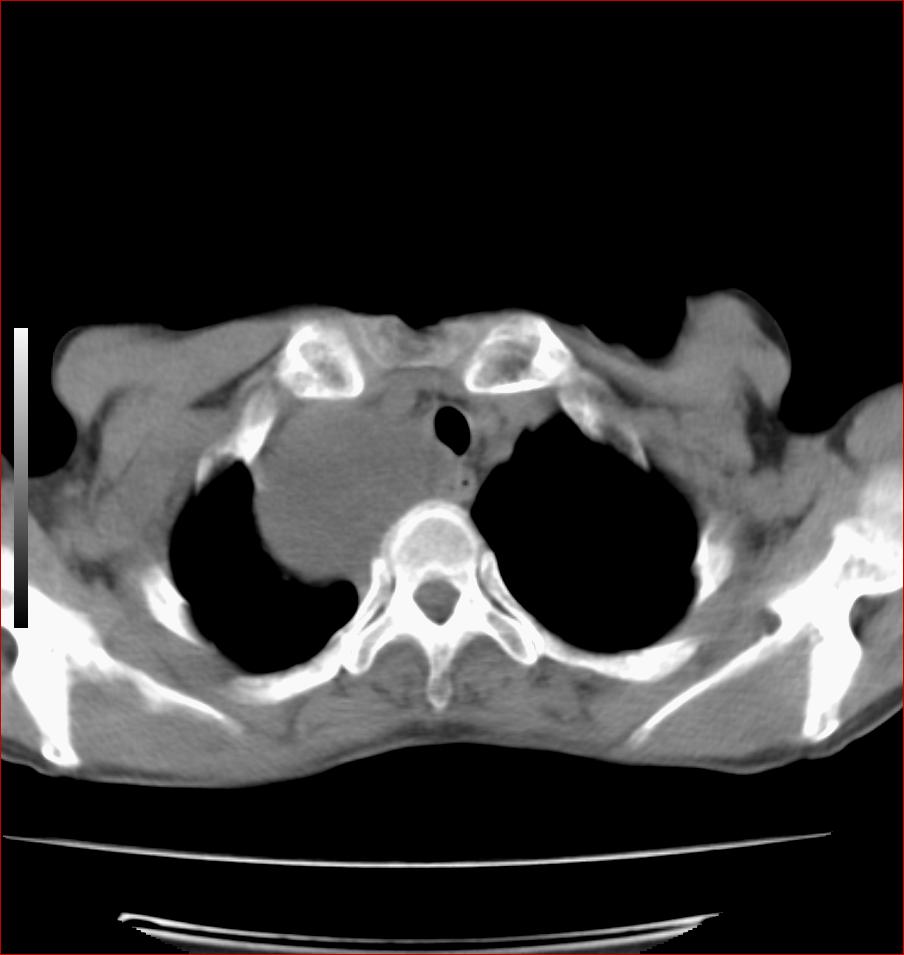

标题: CT17110:F56Y,纵隔囊肿;胸腺?淋巴?请各位老师看看 [打印本页]

标题: CT17110:F56Y,纵隔囊肿;胸腺?淋巴?请各位老师看看

女性患者 56 咽痛伴声嘶10+天入院。

右上纵隔囊性占位性病变;考虑支气管囊肿可能。

病变紧贴气管右壁,两者相互压迫,考虑支气管囊肿!

见相互挤压征,考虑气管囊肿,建议ct增强扫描